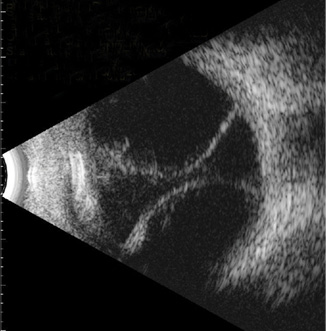

Retinal detachment

Retinal detachment on B-scan appears as a bright, V- or Y-shaped highly reflective membrane that moves independently with eye movement and remains tethered at the optic disc.